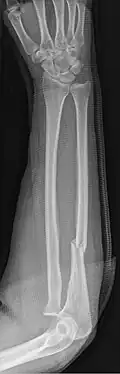

Monteggia Fracture (type of ulna fracture)

An ulna fracture is a break in the ulna bone, one of the two bones in the forearm.[2] It is often associated with a fracture of the other forearm bone, the radius.[1][3]

Fractures of the ulna can occur at different levels of the bone: near the wrist, in the middle or near the elbow.[2] The fracture may be confined to the ulna or accompanied with damage to the radius or the wrist or elbow joints.[2]